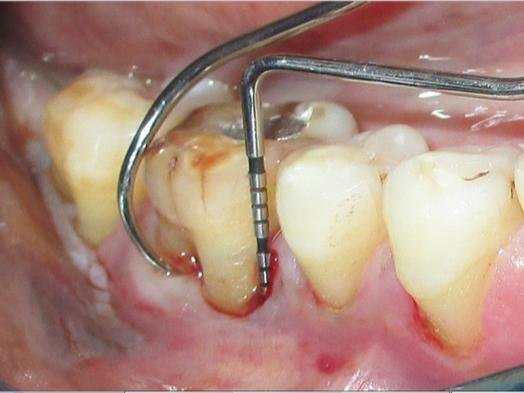

Dental professionals may use probing in order to detect the defects. They use an instrument known as the periodontal probe, where they can explore the areas that situate beneath the teeth and gums, identifying bone loss.

Various x-ray images are also used for diagnosis, in order to detect the loss of the bone in that area. in many x-ray images, it might look almost translucent between your roots.